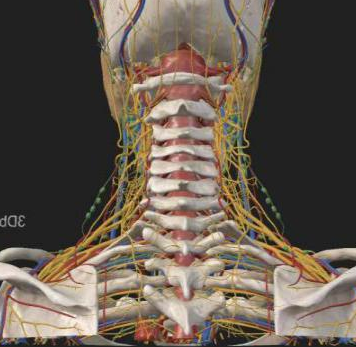

看似确定了治疗方向,真正的难题才刚刚开始。该手术区域解剖结构极其复杂,毗邻人体重要的神经、血管,堪称脊柱外科的“珠峰”。

尤其是C7-T2椎弓根螺钉置入环节,传统手术极度依赖术中C臂透视,却因肩部遮挡,透视、定位极为困难,不仅手术视野受限、置钉难度陡增,螺钉还极易误入椎管,导致术中减压不充分,手术效果完全依赖主刀医生的丰富经验和精湛技术,是业内公认的“硬骨头”手术。